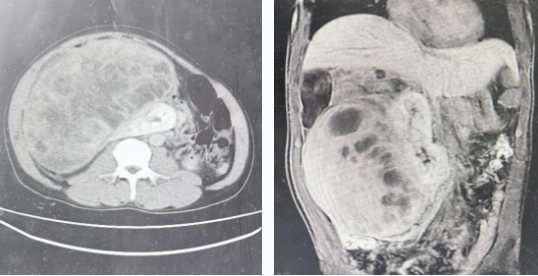

患者因“腹胀伴无法进食10天”急诊入院。入院时,患者腹部异常膨隆,状如足月妊娠,由于肿瘤严重压迫胃肠道,生活质量极差,身体极度虚弱。检查结果显示,腹腔内藏匿着一个巨大的占位性病变,并已引发不全性肠梗阻,病情危重。

术中发现,肿瘤约36 * 25 * 16cm,与周围组织粘连致密。手术团队需要在布满血管神经的“雷区”中小心推进。凭借对人体解剖的烂熟于心,专家们层层分离、止血,历时数小时,最终将这颗重达4.43公斤的“炸弹”完整摘除,并完美保留了肾脏、肠道等重要脏器。